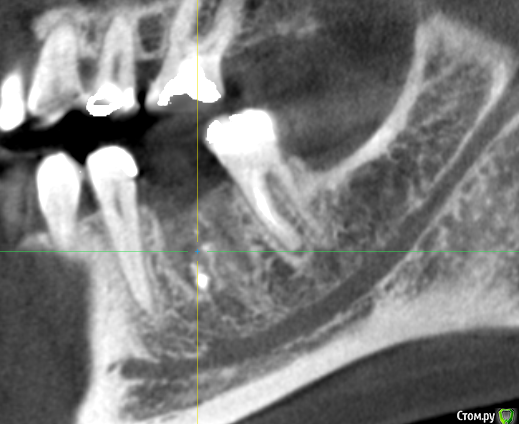

It'sGeorgy Опубликовано 20 января, 2020 Поделиться Опубликовано 20 января, 2020 Дабы не создавать новую тему:Здесь стоило заморачиваться? Ссылка на комментарий

dok1 Опубликовано 20 января, 2020 Поделиться Опубликовано 20 января, 2020 От объема, капсулы. Чуйки , в конце концов . Можно поиграть положением импланта и в первом и во втором случаях. Обойти дегко и там и там 2 Ссылка на комментарий